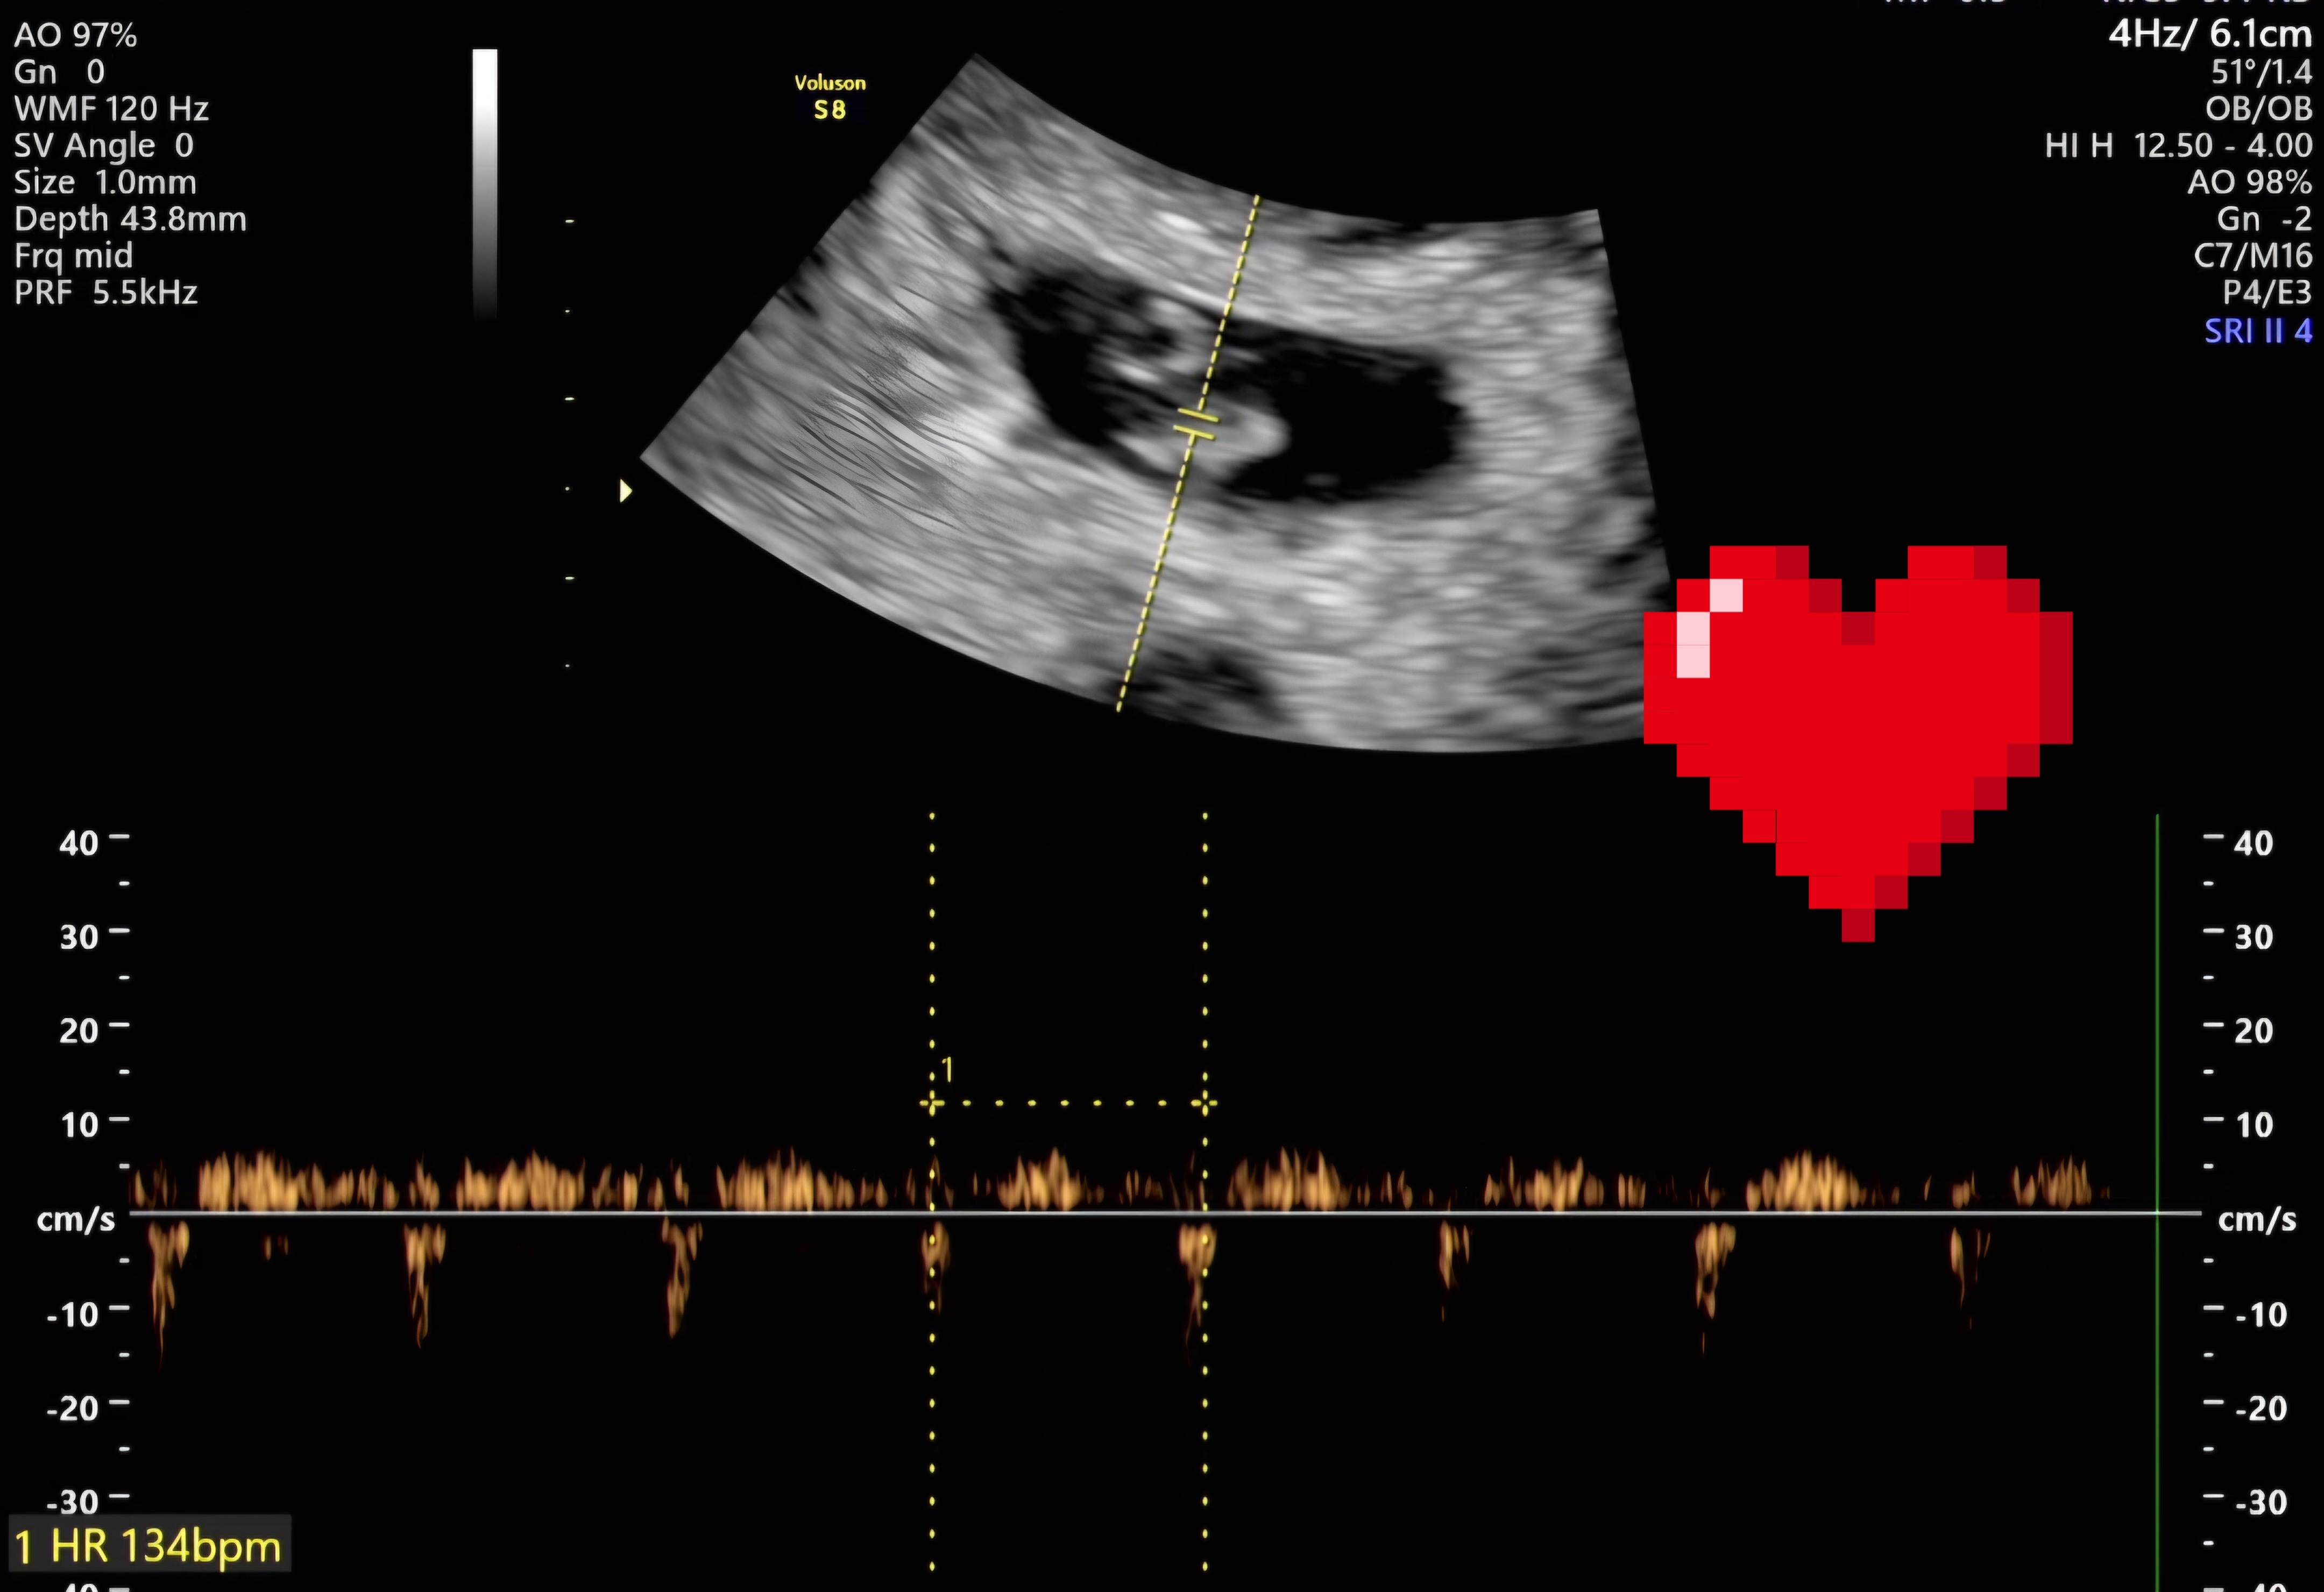

| 가슴 떨리는 임신 이야기를 공유해 주세요. | 저희 부부는 남성요인과 여성의 자궁내막증 수술 이력(한쪽 난소 일부만 남은 상태), 지속적인 재발, 그리고 40세에 가까운 나이라는 여러 조건 속에서 임신이 쉽지 않은 상황이었습니다. 혼인 후 6개월 자연임신을 시도한 뒤 바로 서울아이비에프여성의원을 찾아 검사를 받았고, 배란 유도 치료로 3회 자연임신 시도, 자궁경 폴립 제거, 인공수정 1회 후 시험관 시술을 진행하게 되었습니다. 난자 채취 이후 몸 상태 회복을 위해 원장님께서는 2개월 쉬고 오라고 하셨었는데 제가 느끼기에 괜찮다고 생각될 때를 기다리다보니 6개월정도를 충분히 휴식하고 내원하게 되었습니다. 그후 준비가 됐을 때 배아를 이식하고, 시험관 1차만에 아랫배를 콕콕 쑤시며 쪼꼬만 아기가 저희를 찾아와주었답니다. 기대가 크면 실망도 크니까, 1차 피검사 전날 잠은 한숨도 못 잤지만 임신테스트기는 안 하고 내원했거든요. 진료실에 들어가는 순간 이경훈 원장님께서 피검사수치를 보여주시면서, "축하드립니다 임신되셨네요~!" 하시는데, "어머! 정말요?" 하는 말이 저절로 나왔어요. 2차 피검사, 아기집 보는 날, 심장소리 듣는 날까지, 제 머릿속엔 생각을 많이 하지 않았어도 몸이 너무 긴장을 해서, 잠 한숨 못자고 심장 부여잡고 갔었네요. 가족들에게도 섣불리 말하지 못하고 끙끙 앓고 있던 불안한 마음이, 심장소리를 확인하는 순간 탁 풀려버리고, 안도의 미소가 지어졌어요. 남들은 심장소리 들을 때 눈물 흘린다던데, 저는 가족들에게 아기 소식을 알리면서 눈물파티 했네요 ; _ ; 40주의 여정 중 이제 7주차이지만, 무사히 출산까지 이어지길 기도하고 또 기도합니다 :) |